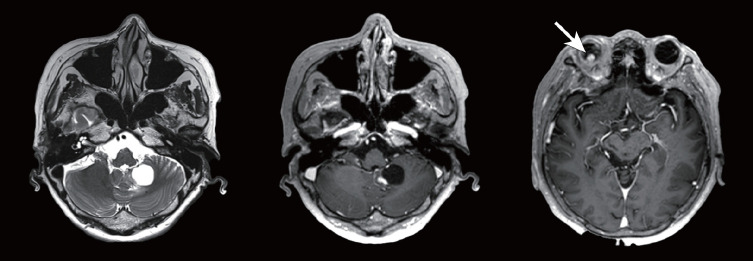

Abstract Image